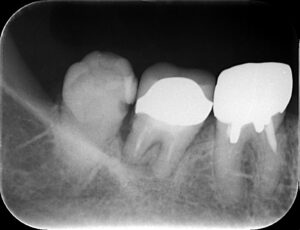

一番左の歯が親知らずで虫歯もあり抜歯となりますが

根が曲がっていることが分かりづらいです。